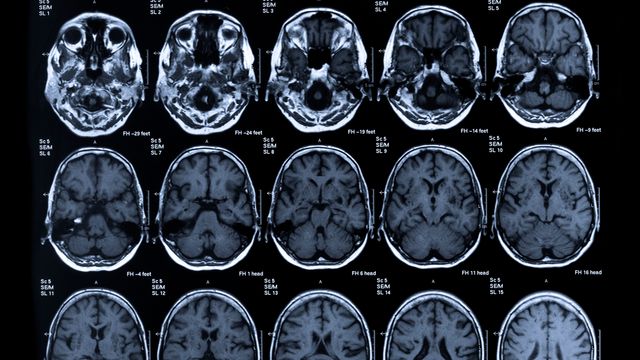

Neuroimaging

This page provides educational resources, events, news and products related to neuroimaging techniques and applications, including MRI, fMRI, CT, PET, DTI and MEG imaging in health and disease.